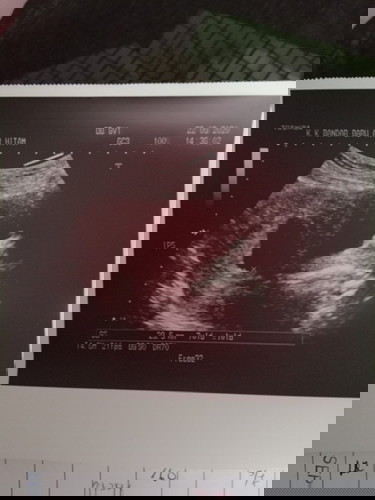

Ini kantung sy masa 8 weeks sis. Nampak kantung je. Repeat scan 20 weeks dah nampak baby berenang. Think positive. Jgn sedih2 ya.